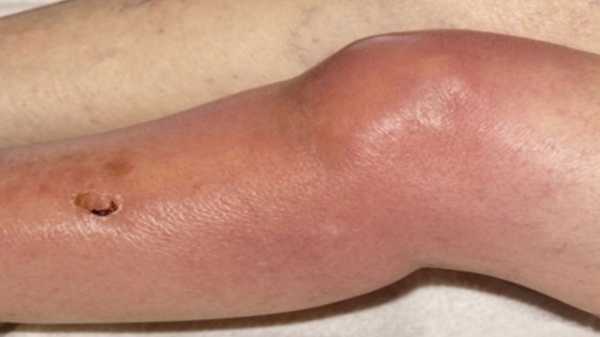

- Покраснение, повышение местной температуры — характерно только для артрита, так как дегенеративное заболевания протекает по типу асептического (без инфекционного) некроза.

Покраснение с отечностью в области сустава — симптом артрита.

- покраснение и отечность в области сустава;

- метеозависимость;

- При остром воспалении кожа на суставе становится ярко гиперемированной и горячей на ощупь.

- Если артрит относится к разновидности, вызванной инфекцией. Страдает общее состояние больного, начинается интоксикация, которая сопровождается лихорадочным состоянием.